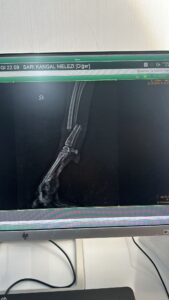

This dog, who came to the shelter with a broken leg, had surgery at Cadde Clinic. He’s doing well. He’s starting to walk again. Unfortunately, we don’t have a place to put him, so he’ll be returning to the shelter. He’ll be housed in a special place at the shelter until he can walk normally again. He’s a large dog suitable for shepherding sheep and cow farms. Male. 30 kg. 5-6 years old. Available for adoption from the shelter. We desperately need your support to care for this dog and many more. Please help us within your budget, so we can help them too.